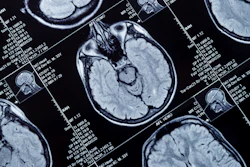

Bracco Imaging is partnering with NYU Langone Health on a multiyear research agreement aimed at advancing innovation in medical imaging.

The collaboration will focus on MRI, photon-counting CT (PCCT), targeted ultrasound, and AI-enabled PET/CT and MRI image analysis, according to the companies. It is designed to accelerate development and optimization of advanced imaging technologies, with the goal of supporting precision medicine and clinical decision-making, they said.